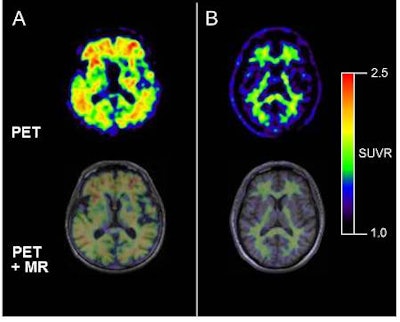

Florbetaben is a PET radiopharmaceutical designed to bind to beta-amyloid clusters in the brain. Beta amyloid has been linked to the development of Alzheimer's disease and other neurologic conditions. A PET scan would detect the uptake of florbetaben as it attaches to beta-amyloid plaques to identify its presence in various brain regions.

| Axial florbetaben brain PET images (top) and co-registered PET/T1-weighted MRI (bottom), each of a typical Alzheimer's disease patient (A) and a typical healthy control (B). Axial slices are at the level of the basal ganglia. PET images are 90 to 110 minutes after injection; standardized uptake value ratio (SUVR) data are with the cerebellar cortex as the reference region. Image courtesy of Piramal Imaging. |

According to Piramal Imaging, initial studies of florbetaben have shown that it can be administered intravenously in very small doses. Its rapid evacuation from a patient's body and the low dose injected (due to its relatively short half-life of 110 minutes) would make the tracer suitable for clinical use.

Along with florbetaben-PET images, researchers followed up with MRI exams to correlate the results. To determine which areas of the brain were positive or negative for beta-amyloid deposits, researchers conducted blinded reads on all six regions and obtained images of each brain for pathologists to measure the activity of the beta-amyloid protein.